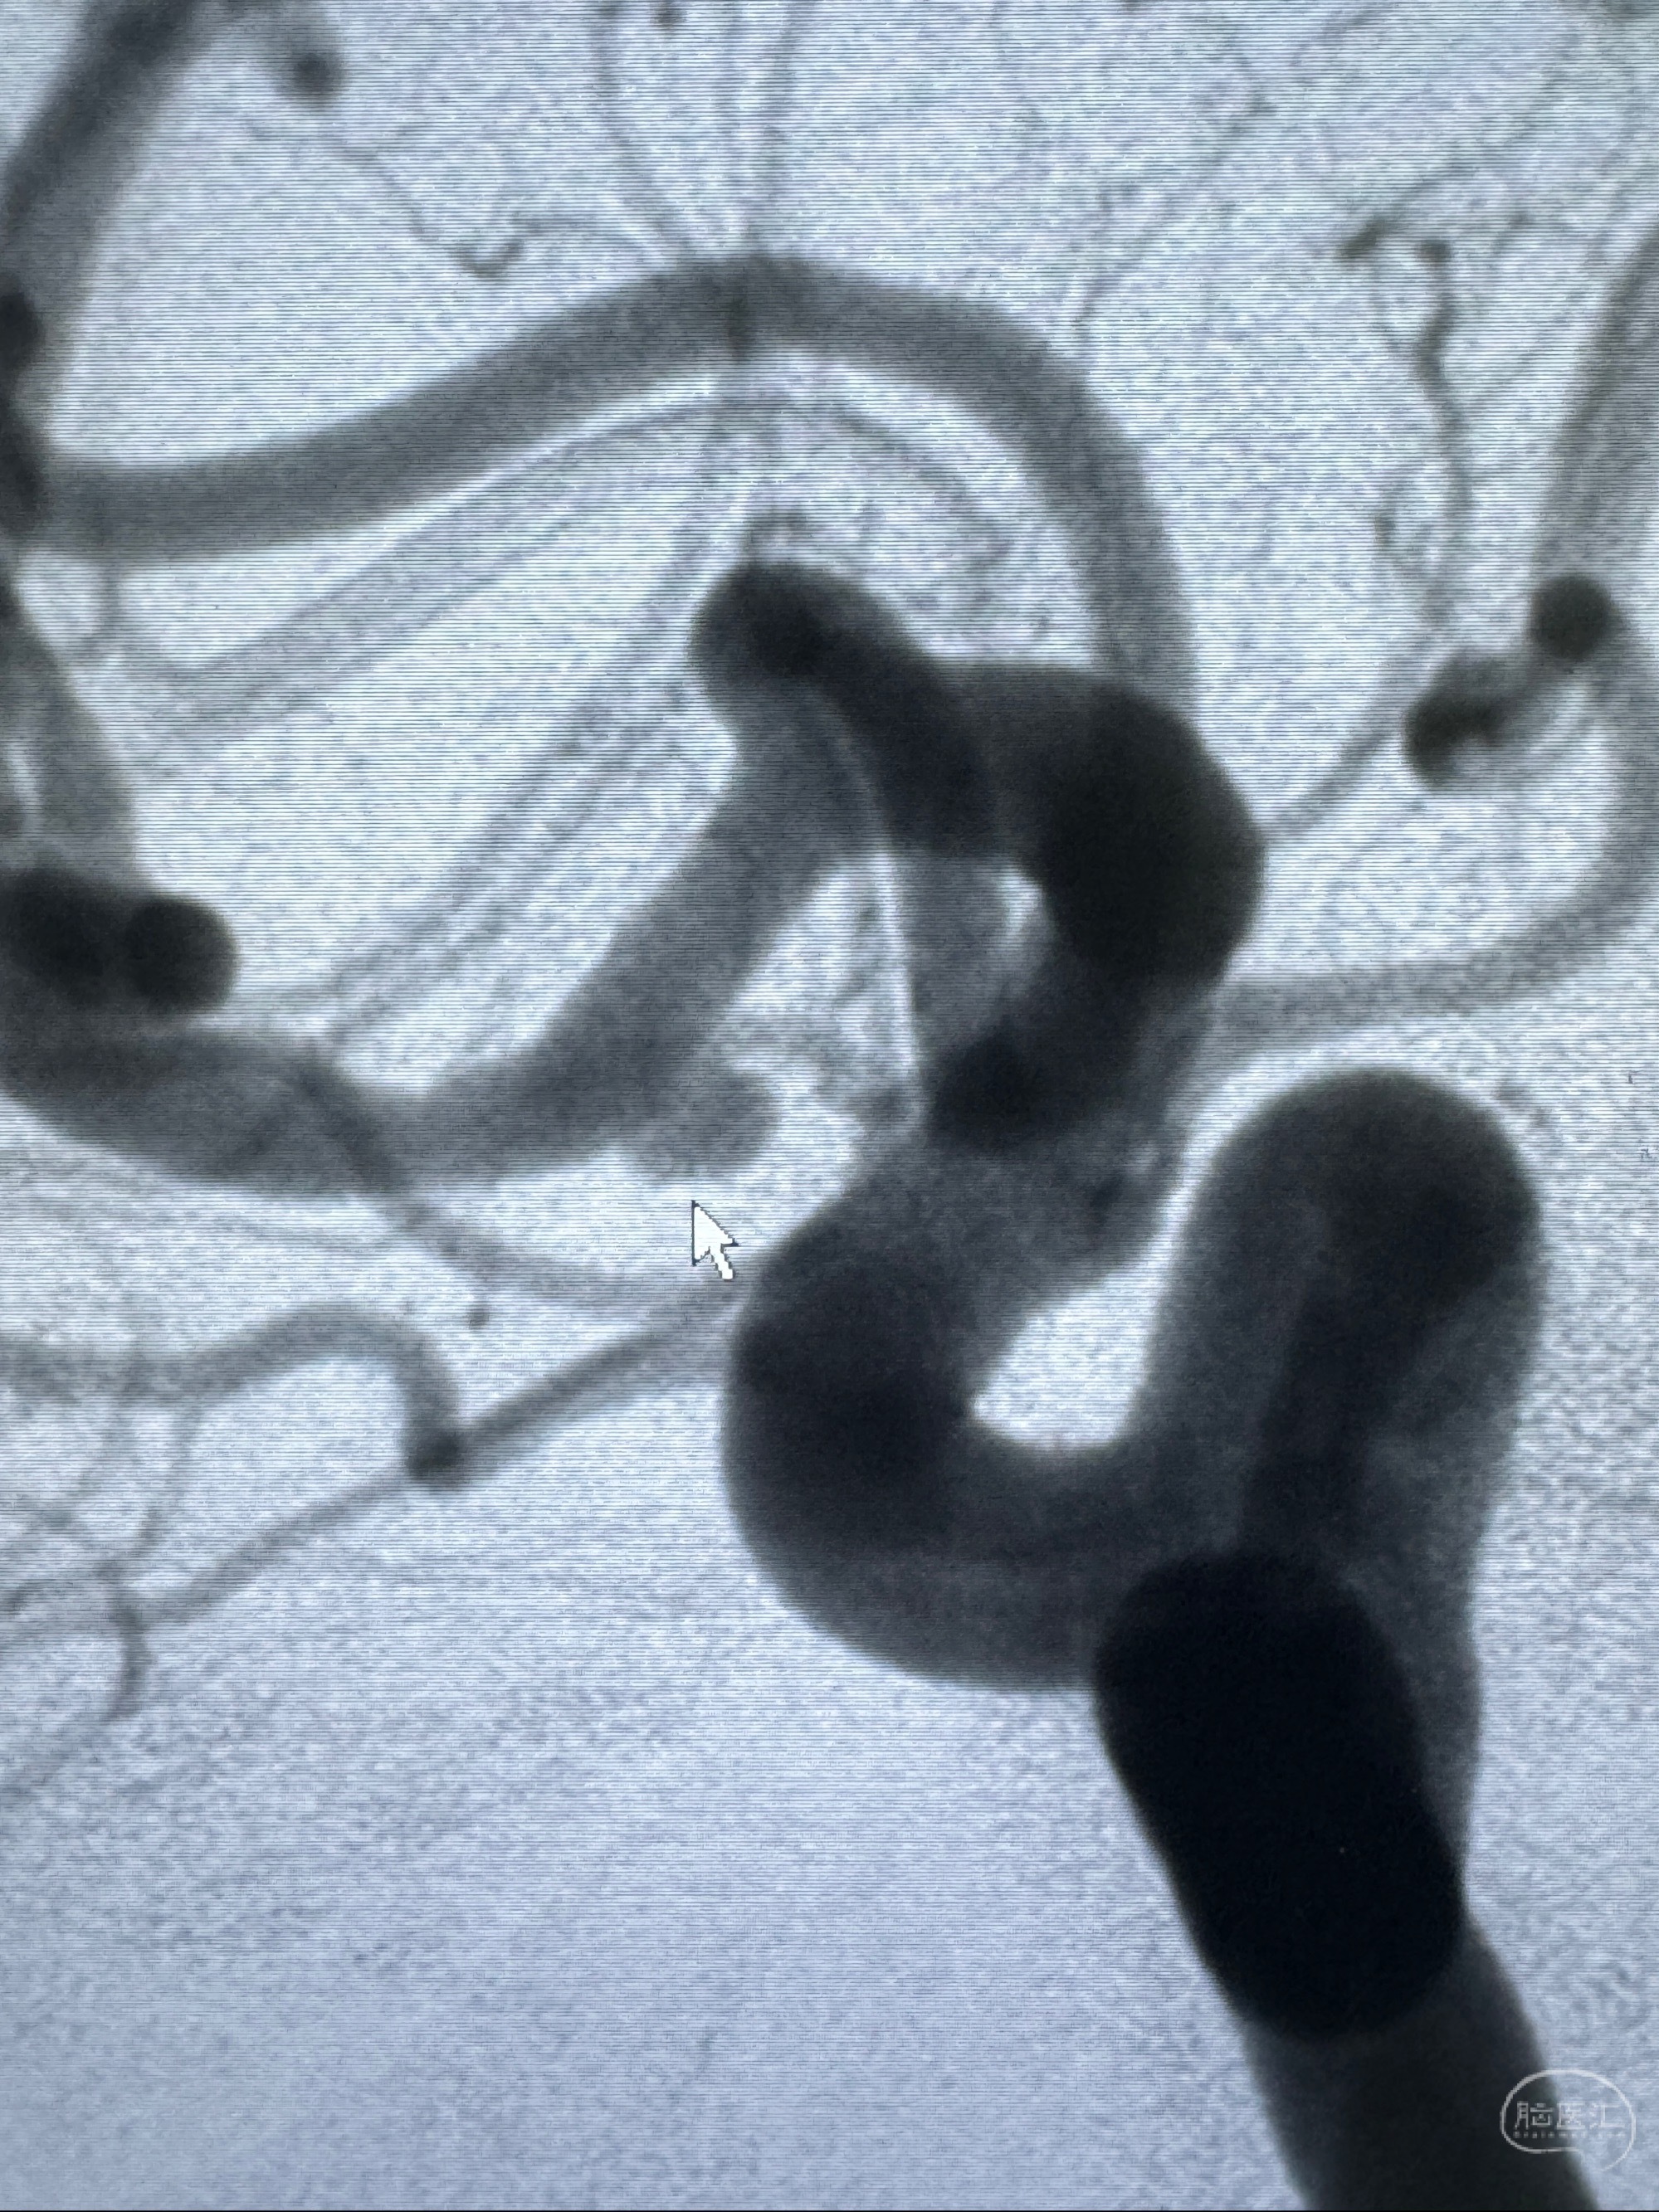

2023-11-24DSA:右侧大脑中动脉下干起始部动脉瘤,约2.3*2.5mm,形态规则